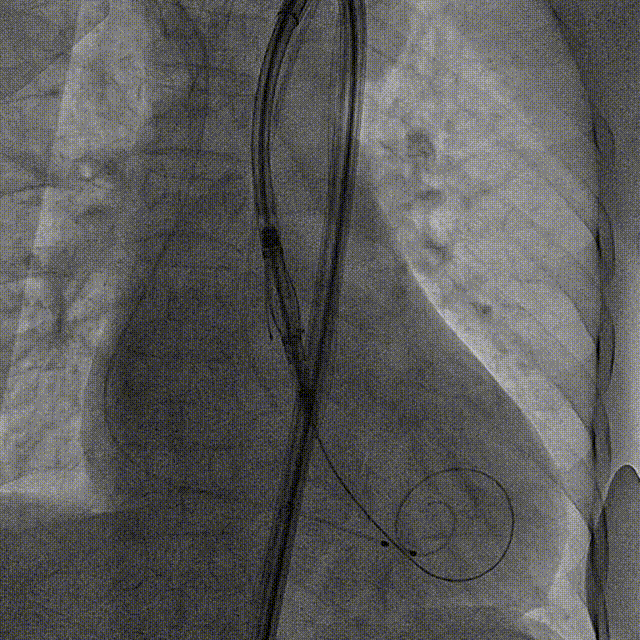

术前右窦中心造影

大鞘植入

瓣膜调弯解离

定位键窦对齐验证

定位键入窦验证

深度检查

一键释放

后扩后造影